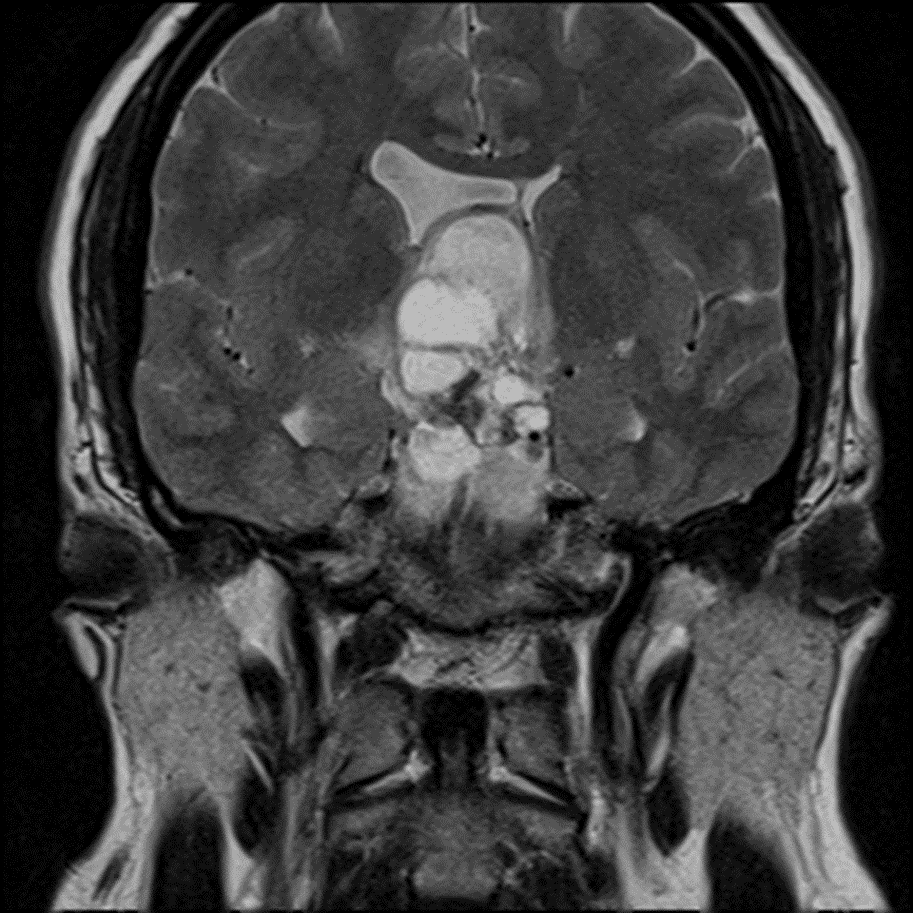

MRI

- Mixed cystic and solid suprasellar mass measuring 3.5 x 2.3 x 4.2 cm with solid enhancement of the solid components and peripheral enhancement of the cystic components

Multiple T2 hyperintense cystic components.